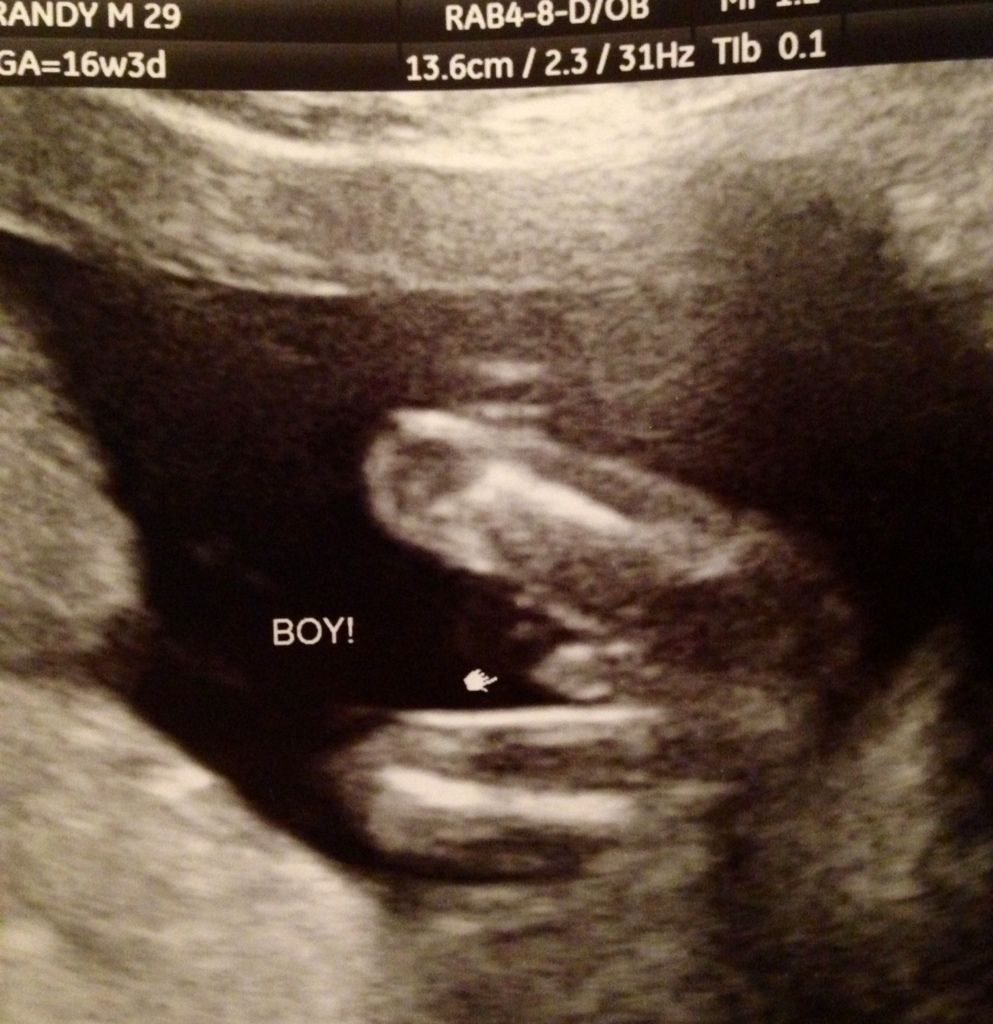

From community.babycenter.com

Tech says BOY I don't see scrotum?! BabyCenter Baby Boy Rash Under Testicles A hydrocele carries the same risk as a hernia. Common causes for scrotal redness include. it isn't painful, but your baby's testicles may look swollen. scrotum symptoms include pain and swelling of the testicle, itching and rash. Genital dermatitis is a skin condition that affects the penis, scrotum, groin, skin around the opening of the anus and the. Baby Boy Rash Under Testicles.